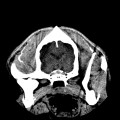

CT - angiografie (kočka)